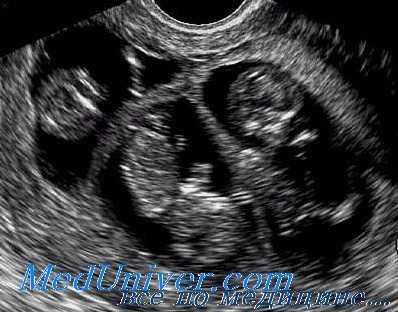

Диагностика многоплодия

Основным методом диагностики на ранней стадии является ультразвуковое исследование. При проведении исследования уже на 5й неделе можно обнаружить 2 или более плодных яйца, располагающихся в полости матки. На более поздних сроках можно увидеть структуру эмбрионов.

Перечисленные симптомы - повод для того, чтобы заподозрить многоплодие. Диагноз в обязательном порядке необходимо подтвердить с помощью УЗИ, ибо только данное исследование является достоверным.